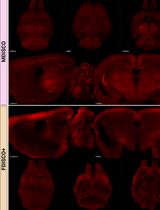

推进 EAE 动物模型研究:一种无需百日咳毒素的多发性硬化免疫建模方案的建立

Advancing EAE Modeling: Establishment of a Non-Pertussis Immunization Protocol for Multiple Sclerosis

SG Shruti Gupta

SA Sreejita Arnab

ES Elena Stehle

KN Kayla L. Nguyen

28 Views

Feb 5, 2026

Experimental autoimmune encephalomyelitis (EAE) is a widely used rodent model of multiple sclerosis (MS), typically induced with pertussis toxin (PTX) to achieve robust disease onset. However, PTX has been shown to exert broad immunomodulatory effects that include disruption of G protein-coupled receptor (GPCR) signaling, altered T-cell response, and exogenous suppression of regulatory T cells, all of which are not present in human MS pathophysiology. Moreover, PTX also obscures the sex differences observed in MS, limiting the translational value of EAE models that rely on it. Given EAE’s widespread use in preclinical therapeutic testing, there is a critical need for a model that better recapitulates both clinical and immunological features of MS without PTX-induced confounds. Here, we demonstrate a non-pertussis toxin (non-PTX) EAE model in C57BL/6 mice, using optimized concentrations of complete Freund’s adjuvant (CFA), Mycobacterium tuberculosis, and myelin oligodendrocyte glycoprotein (MOG35-55) peptide. This model recapitulates hallmark features of MS that include demyelination, neuroinflammation, motor deficits, and neuropathic pain. Importantly, it retains sex-specific differences in disease onset and pathology, providing a more physiologically and clinically relevant platform for mechanistic and translational MS research.